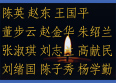

美国之音深入报道中共活摘器官